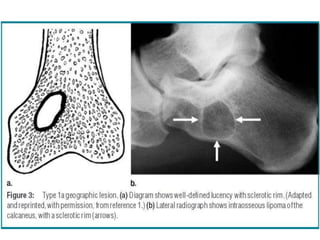

Geographic Pattern

Radiological Findings • Exactlocation of the tumour • Borders of the tumour • Pattern of bone destruction • Matrix formation/mineralization • Periosteal reaction